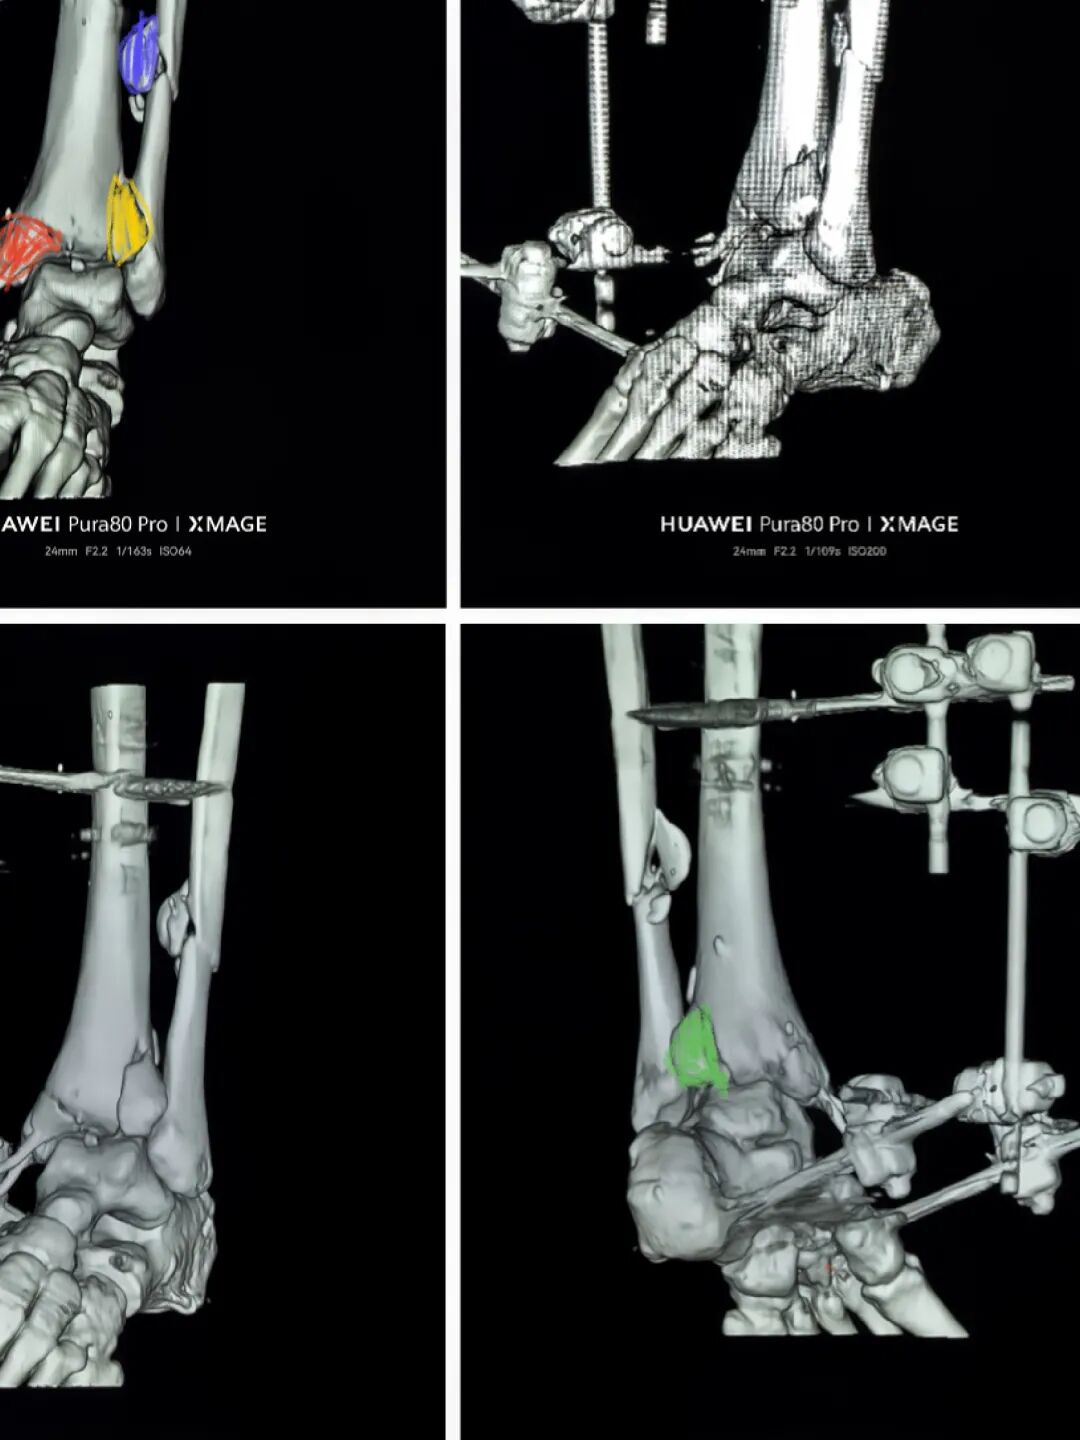

下胫腓关节复位良好

但前侧Chaput骨块

后侧volkmann骨块都移位